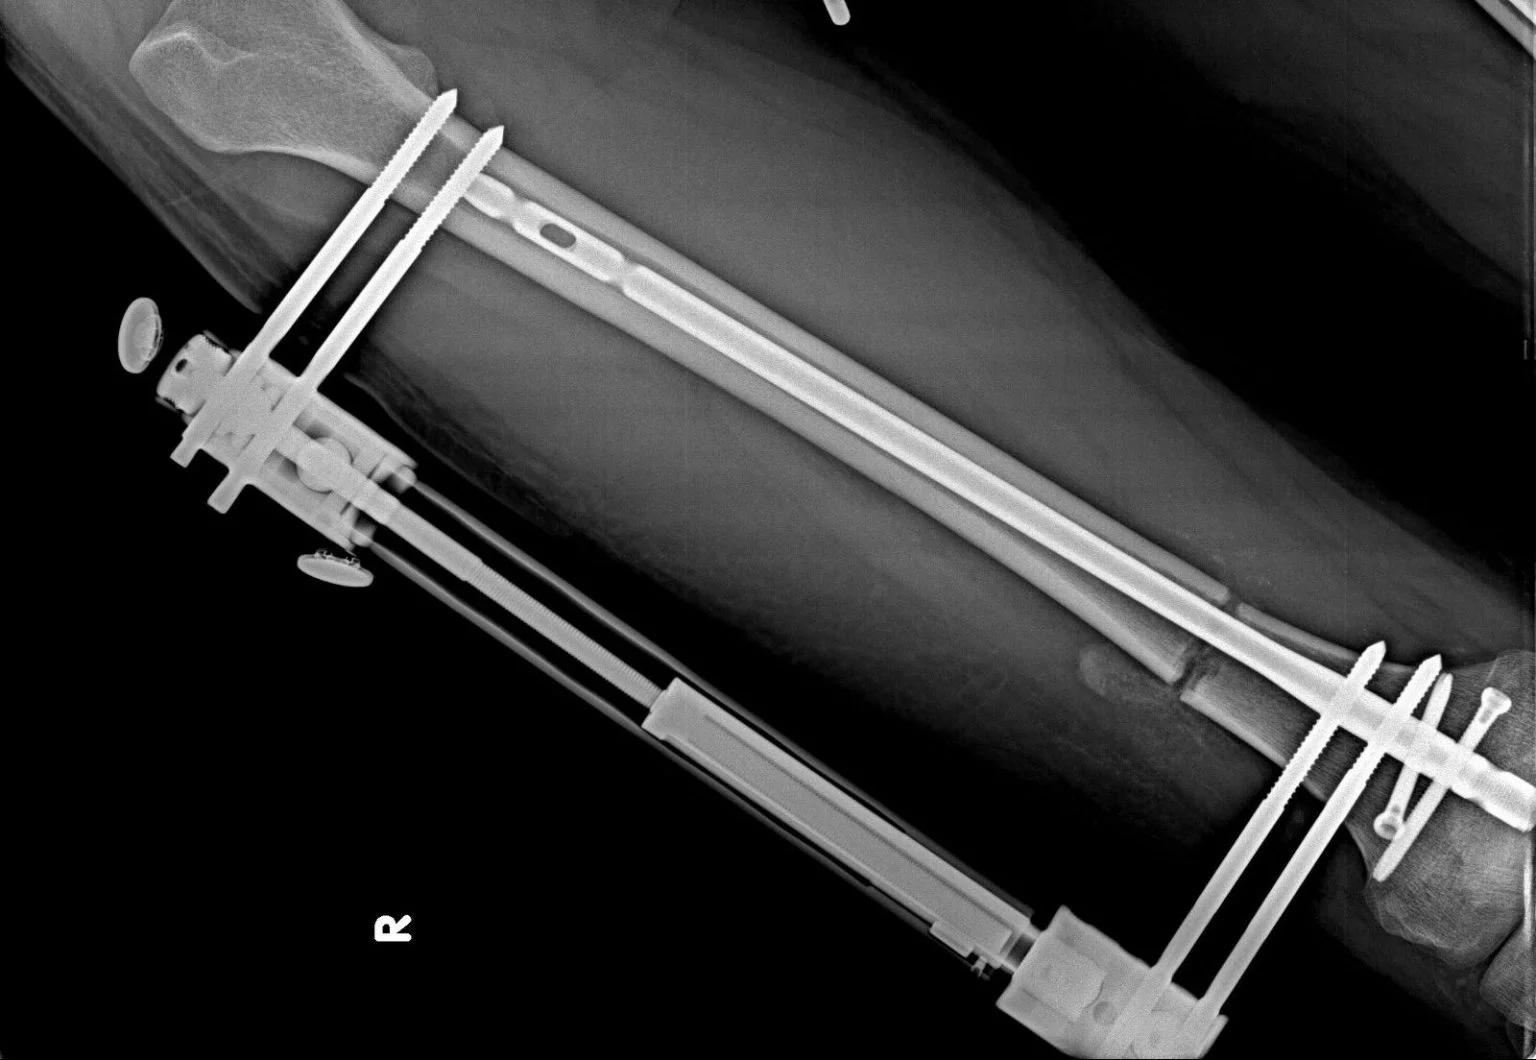

Bu sistem, uzatma ameliyatı sırasında kemiği dışarıdan destekleyen güçlü bir yapıdır. Uzatma süreci boyunca kemiğin stabil kalmasını sağlar ve doğru şekilde kaynamasına yardımcı olur.

Kalın metal çubuklardan oluşan dış fiksatör, özel pinler aracılığıyla kemiğe sabitlenir ve böylece kemik güvenli ve kontrollü bir şekilde uzatılır.

Cihaz ameliyat sırasında takılır ve genellikle hedeflenen uzama miktarına ulaşılana kadar yaklaşık 2–3 ay boyunca bacakta kalır. Bu süre boyunca dış fiksatör, kemiğin dengesini koruyarak sağlıklı bir uzama süreci sağlar.

İntramedüller Çivi:

Boy uzatma ameliyatı sırasında kemiği desteklemek ve uzama sürecini güvenli şekilde sürdürmek için kullanılan, titanyumdan üretilmiş yüksek biyouyumlu bir çividir.

Çivinin boyutu, röntgen görüntülerine göre doktor tarafından belirlenir ve genellikle 8.5 mm, 10.7 mm, 11.5 mm veya 12.5 mm seçenekleri kullanılır.

Bu çivi ameliyat sırasında kemik iliği kanalına yerleştirilir ve yüksek biyouyumluluğu sayesinde çevre dokulara zarar vermez, vücut üzerinde olumsuz bir etki oluşturmaz.